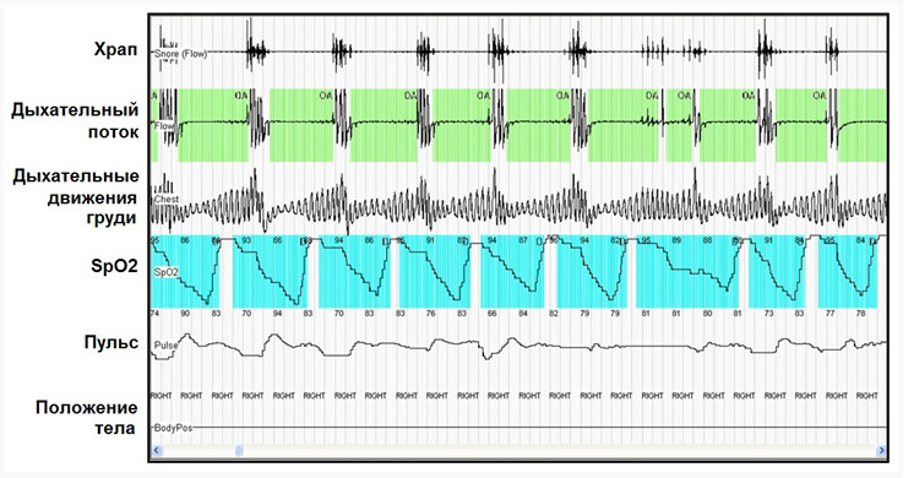

Пример данных кардиореспираторного мониторинга

Основные параметры кардиореспираторного мониторинга:

- характеристики дыхательного потока,

- частота сердечных сокращений,

- наличие и громкость храпа,

- насыщение крови кислородом (сатурация),

- наличие дыхательных усилий грудной клетки и живота,

- положение тела.